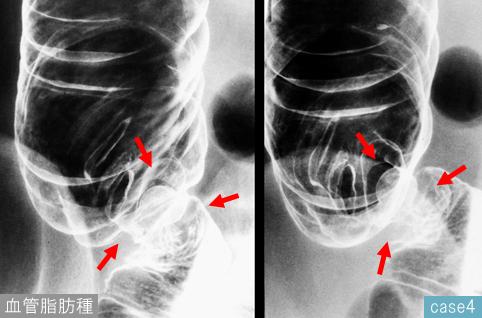

疾病(病理主体)的分类其它/

部位(按器官分)大肠/盲肠

检查方法X线

肿瘤最大直径15~19